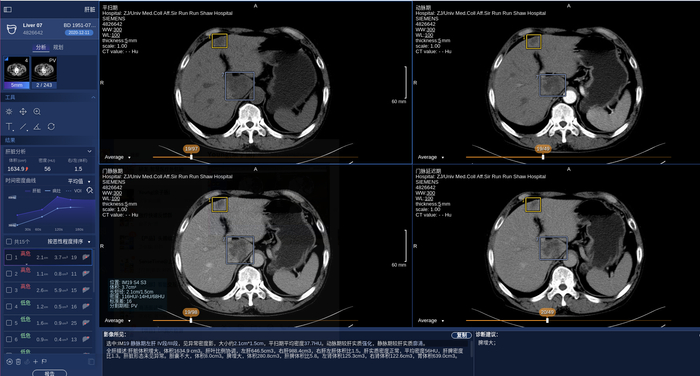

商汤科技SenseCare®️肝脏CT智能临床解决方案产品界面

它能够满足影像科阅片、分析、诊断、报告需求,并通过结合3D术前规划以及愈后康复跟踪,为骨科、肝外科、心内科、病理科、胸外科、放疗科等多个临床科室医生提供智能辅助,覆盖诊疗愈全流程。例如SenseCare®️消化道活检病理辅助分析系统可帮助病理科医生对大量胃肠道活检切片进行早癌筛查和多病种病灶区域勾画,实际应用中阳性切片检出率达到了100%,筛阴率也能够达到90%以上,可以大幅度减少病理医生的工作量。